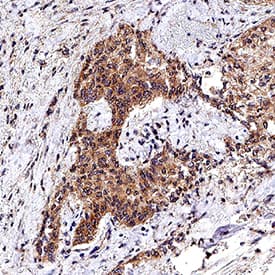

HGF antibody in Human Lung Adenocarcinoma Tissue by Immunohistochemistry (IHC-P).

HGF in Human Lung Adenocarcinoma Tissue.

HGF was detected in immersion fixed paraffin-embedded sections of human lung adenocarcinoma tissue using Mouse Anti-Human HGF Monoclonal Antibody (Catalog # MAB294) at 15 µg/mL overnight at 4 °C. Before incubation with the primary antibody, tissue was subjected to heat-induced epitope retrieval using Antigen Retrieval Reagent-Basic (CTS013). Tissue was stained using the Anti-Mouse IgG VisUCyte™ HRP Polymer Antibody (brown VC001) and counterstained with hematoxylin (blue). Specific staining was localized to cytoplasm in cancer cells. View our protocol for IHC Staining with VisUCyte HRP Polymer Detection Reagents.